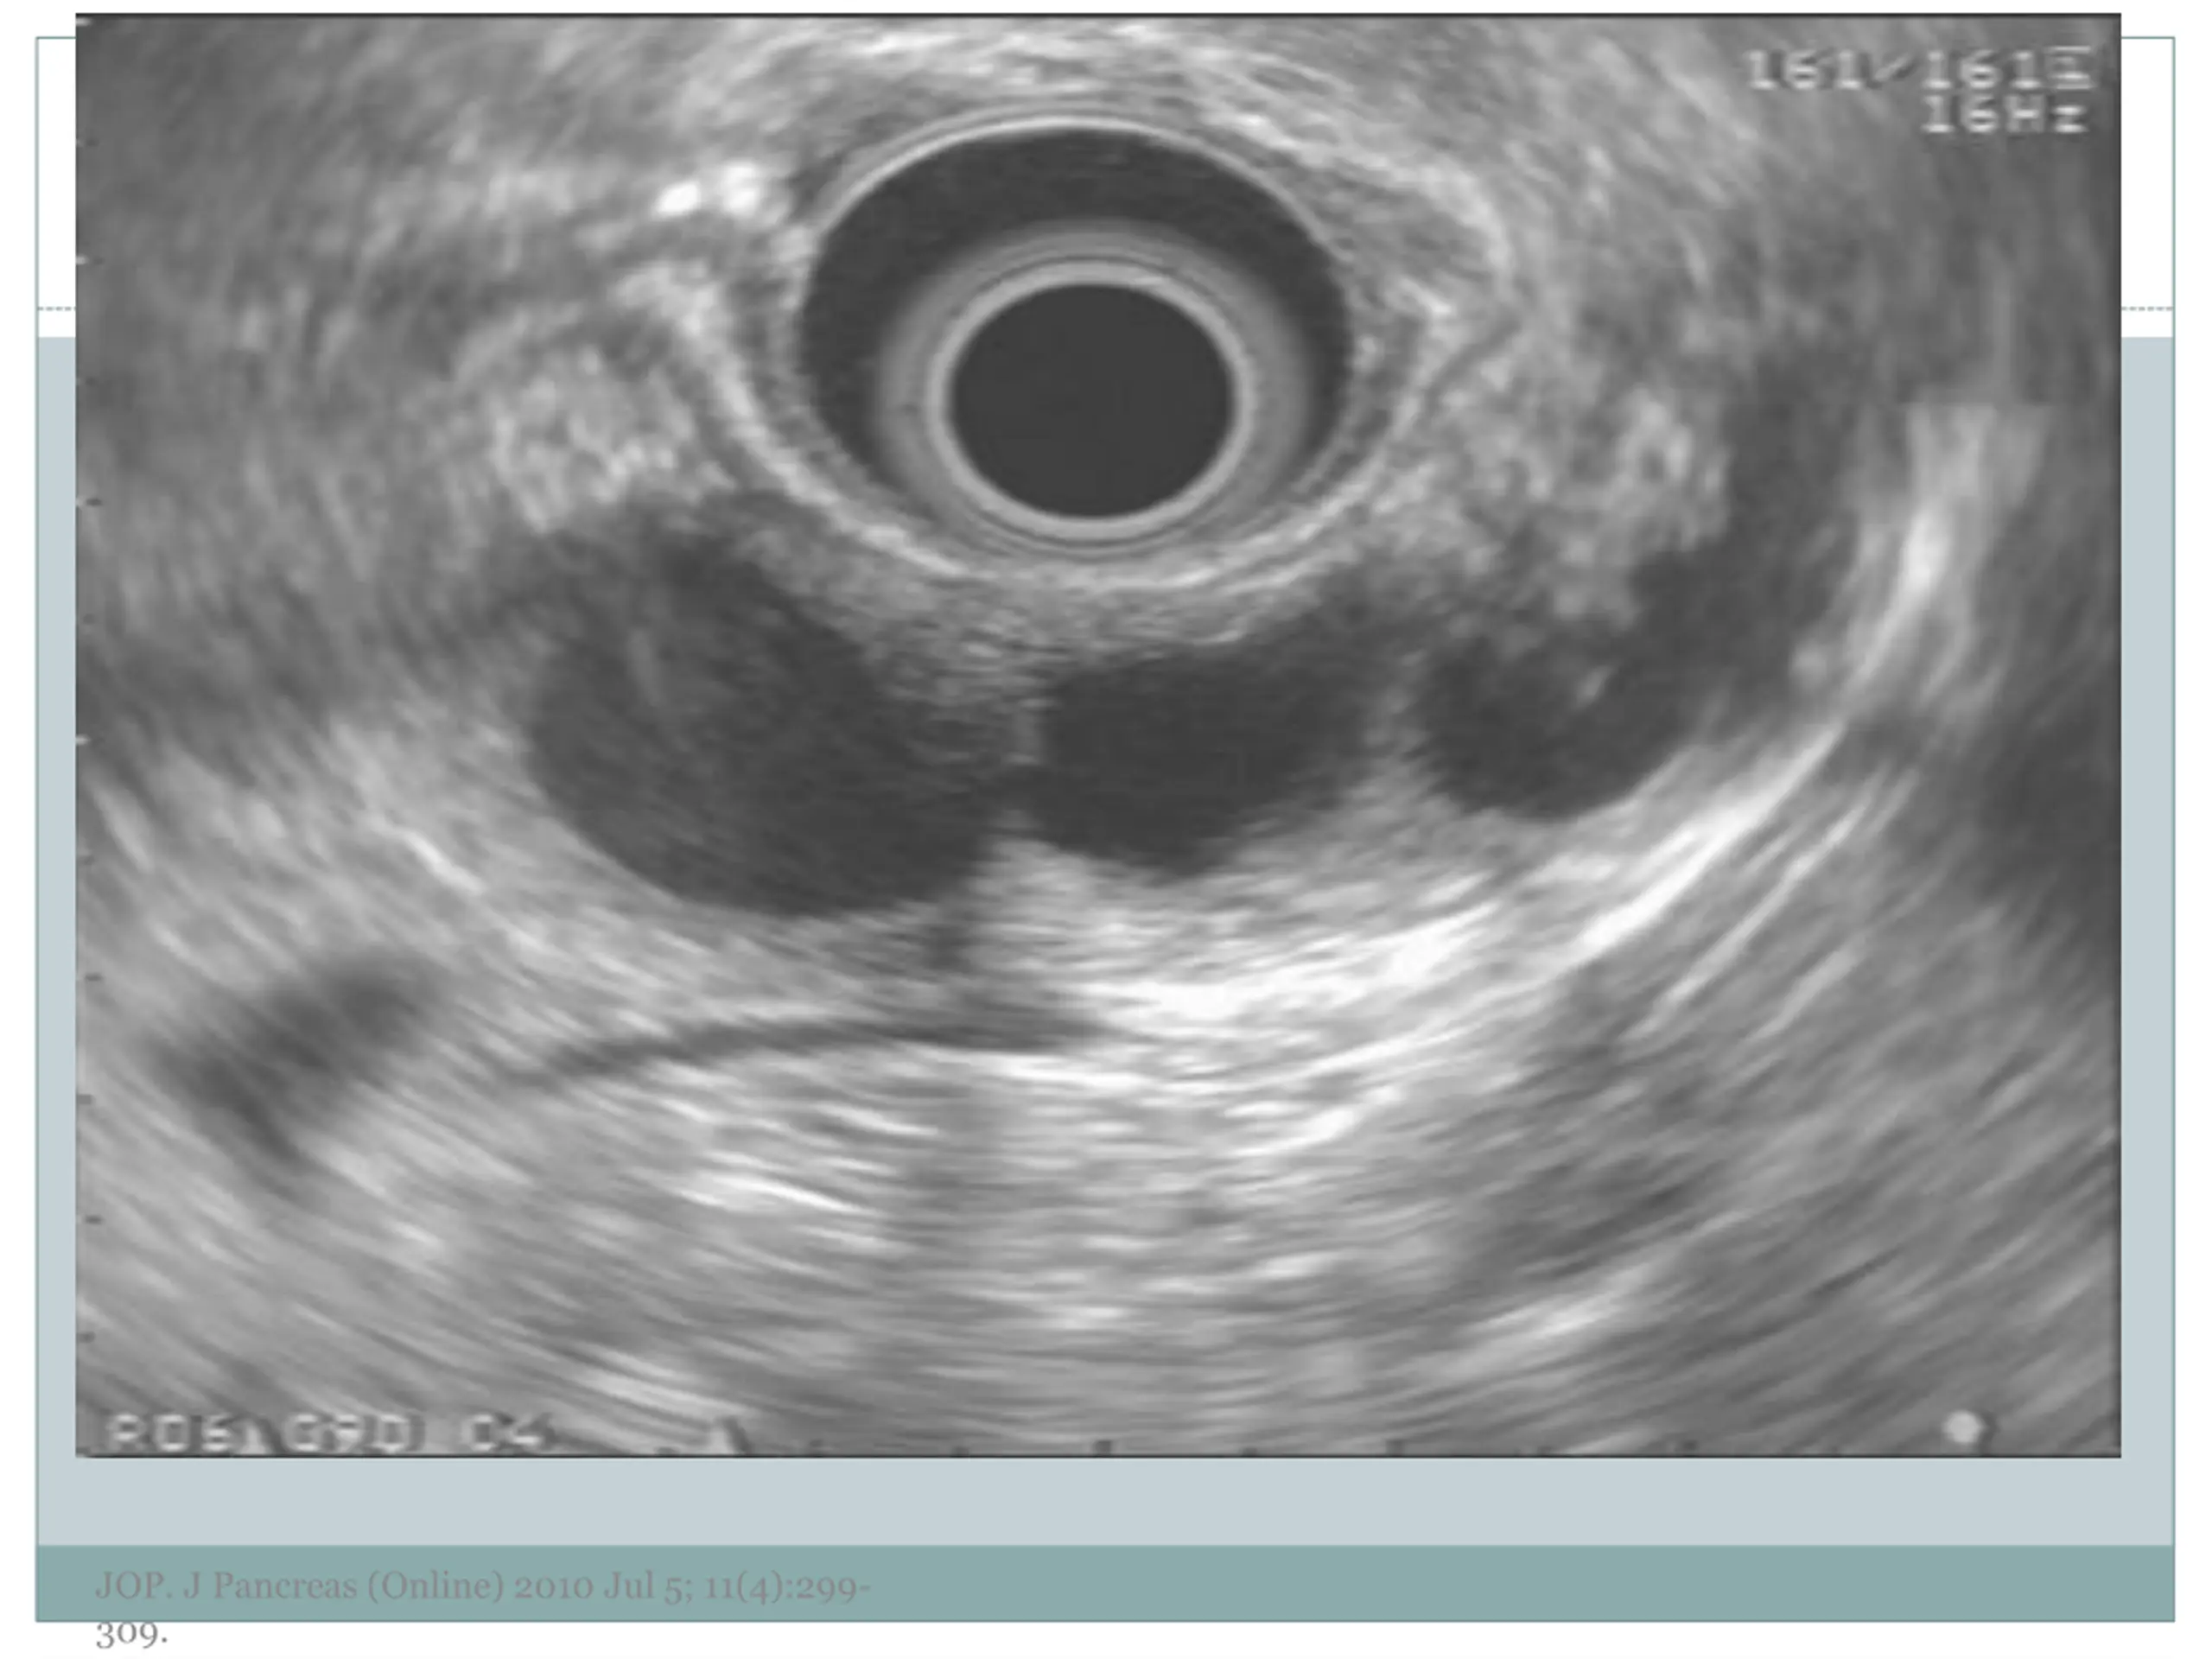

7. EUS Morphology Cyst wall Thick vs. thin Solid component Associated with malignancy Septations Micro vs. macrocystic Ductal abnormalities Main duct vs. side duct Number of cyst Lymphadenopathy EUS morphology can correctly differentiate mucinous from non-mucinous cystic lesions approximately 50% of the time JOP. J Pancreas (Online) 2010 Jul 5; 11(4):299- 309.

10. Examples of Morphology JOP. J Pancreas (Online) 2010 Jul 5; 11(4):299- 309.

11. JOP. J Pancreas (Online) 2010 Jul 5; 11(4):299- 309.

12. JOP. J Pancreas (Online) 2010 Jul 5; 11(4):299- 309.